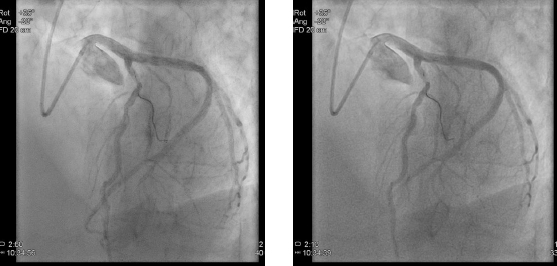

BMI 32の72歳の患者さんの冠動脈造影。マイン タウヌス心臓センターが同条件で撮影。

(左)AlluraClarityを使用し,AlluraXperで通常使用するX線量の50%の線量で撮影した冠動脈造影

(右)AlluraXperで撮影した冠動脈造影